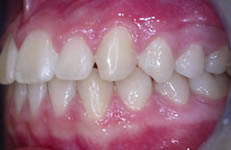

Terapia ortodontica - Prima (FIG 1)

La paziente S.A., di anni 12, presenta morso crociato posteriore monolaterale (fig. 1) dovuto a deviazione della mandibola verso destra in fase chiusura , pertanto le linee interincisive risultano non coincidenti (fig. 2). Si rileva inoltre l’assenza in arcata del canino superiore di sinistra ( incluso) e carenza di spazio per lo stesso (fig. 3 e 4).